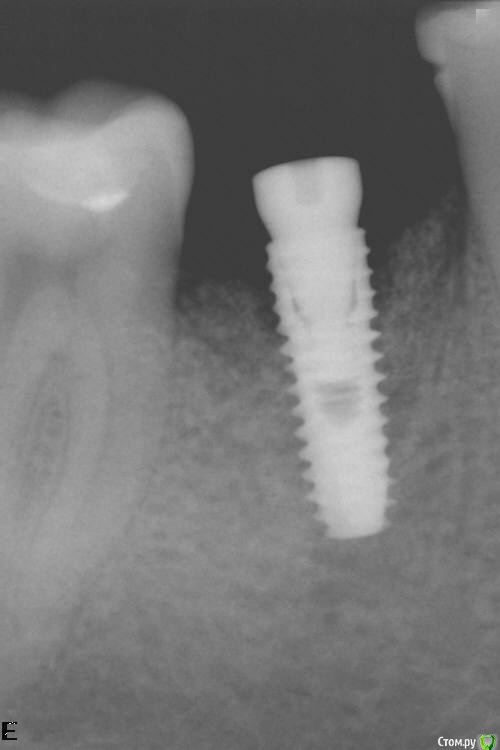

Kirill85 Опубликовано 22 июля, 2019 Поделиться Опубликовано 22 июля, 2019 Добрый день. Ситуация такая, установили имплант и во время приживления имплант оголился. Сейчас установили формировать десны, но десна не наростала и была видна резьба имплант. Сделали пластику десны, после снятия швов десна снова сползла и опять оголяется резьба имплант. Есть ли смысл устанавливать корону на такой имплант или нужно все переделывать? Ссылка на комментарий

Kirill85 Опубликовано 22 июля, 2019 Автор Поделиться Опубликовано 22 июля, 2019 Вот фото и снимок Ссылка на комментарий